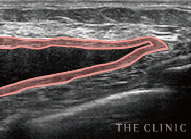

乳腺用の高性能エコーを全院に導入

当院が使用するのは大学病院でも採用されている「エラストグラフィ」。乳がんの検査にも使われている乳腺用エコーです。

乳腺用エコーでしこりを診断

アクアフィリング豊胸やアクアリフト豊胸後の乳房内の状態を、触診だけで正確に把握することは困難です。アクアフィリング豊胸後にしこり化している場合は、位置や数、状態などを調べる必要がありますが、しこりの自覚がない方からのご相談も少なくありません。

その点、THE CLINIC では全院にデジタル乳腺用エコー「エラストグラフィ」を導入。施術前に必ずエコー検査を行い、細かい情報を把握した後、適切な治療方針を決定します。

THE CLINIC ではアクアフィリング豊胸やアクアリフト豊胸後のしこりを確実に溶解・除去するため、必ず乳腺用エコーを使用。最短ルートでしこりを取り除けるので、体への負担を最小限に抑えます。